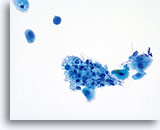

Repair

Criteria to classify a reparative process on Thin Prep slides are similar to the criteria as enumerated in The Bethesda System.

- Minimal nuclear enlargement (11/2 to 2 times normal intermediate cell nucleus)

- Bi and multi-nucleation may occur

- Mild hyperchromasia may be present

- Chromatin finely granular, evenly distributed

- Karyopyknosis and karyorrhexis may occur

- Nuclear membranes smooth

- Prominent single or multiple nucleoli

- Flat sheets with polarity maintained; groups may round up in fluid

- Mitosis and single cells may be noted

- Often accompanied by neutrophils, inflammatory changes and/or organisms